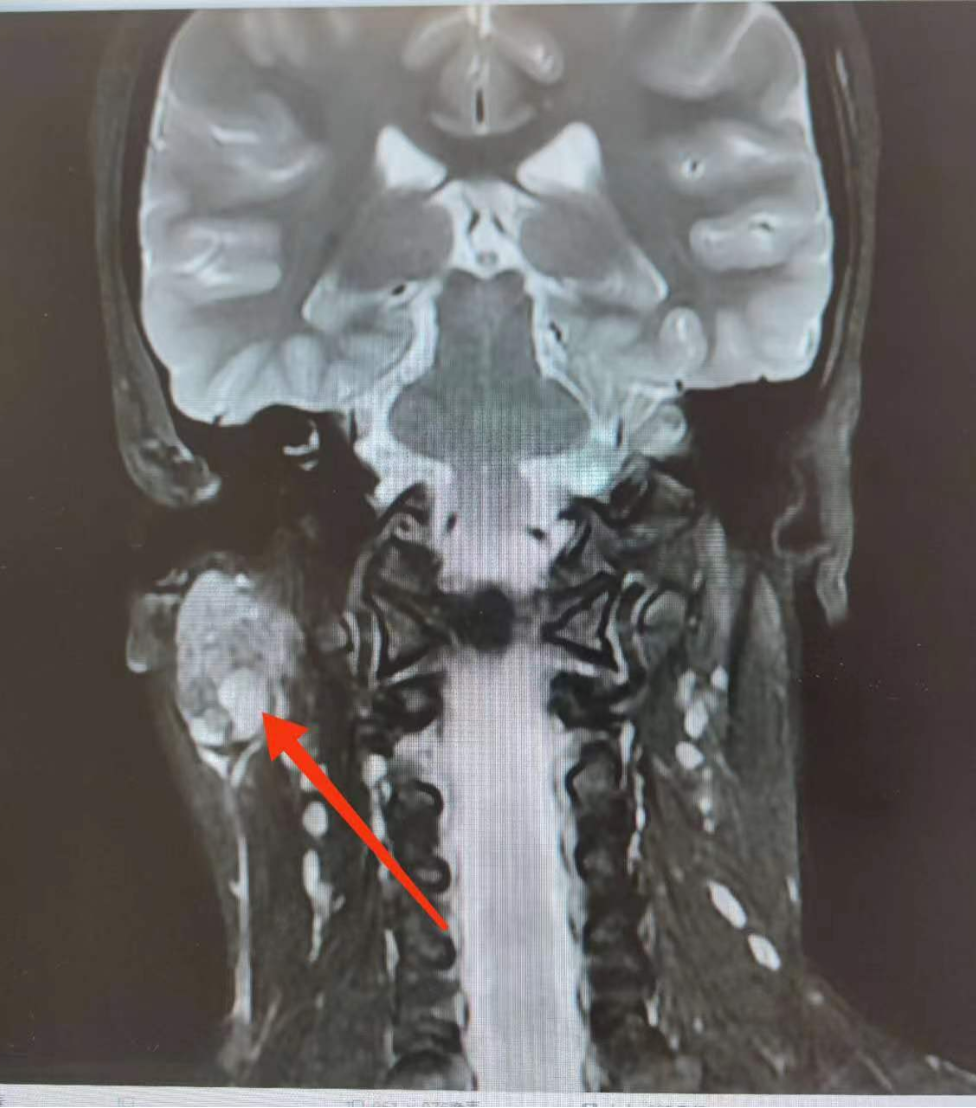

于是家長帶她來到青島市婦女兒童醫(yī)院口腔頜面外科門診就診,MR檢查提示:右側(cè)腮腺內(nèi)見斑片狀、囊狀病變,約2.6*1.6cm大小。醫(yī)生考慮“腮腺區(qū)腫物”,建議玲玲入院手術(shù)治療。

隨后,醫(yī)生為玲玲實(shí)施了右側(cè)腮腺腫物切除術(shù)+面神經(jīng)解剖術(shù),術(shù)后最終病理結(jié)果提示為高分化黏液表皮樣癌,這是一種原發(fā)性唾液腺惡性腫瘤,多發(fā)生于腮腺,且最為常見。經(jīng)過手術(shù)和術(shù)后相關(guān)治療,目前玲玲已順利出院,身體恢復(fù)良好。